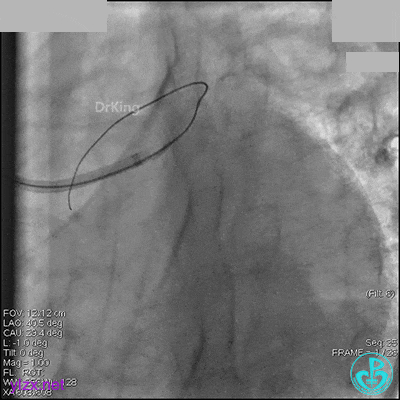

右冠脉中段充分扩张后欲植入3.5×38mm支架时,支架难以通过中远段扭曲处,且指引导管、导丝弹出飞扬。反复尝试导丝重新到达右冠脉远端时通过不顺利,局部造影剂滞留,远端血流接近3级。

右冠脉血流3级,患者无症状,终止手术。